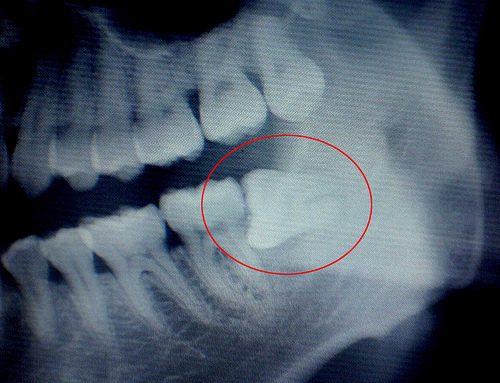

首先,该不该拔看情况:如果智齿生长正常,基本是无需拔除的,智齿发炎主要因为智齿在发育过程中,顶破了牙龈肉等组织,致使牙龈疼痛肿胀,这种情况可以通过服用消炎止痛药进行缓解。但如果牙齿已经阻生歪斜,向其他方向生长,则一定要拔!切勿抱着忍忍就好的心态想着熬到它完全萌出就好,否则不但在其萌发过程中会导致反复性疼痛,而且即使完全萌出后,因为生长歪斜,也只会压迫其它牙齿,造成牙列拥挤,除了大大妨碍口腔清洁,还影响牙齿健康。